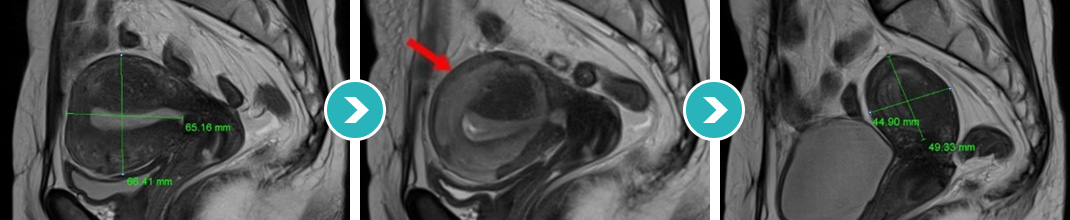

6cm 크기 자궁후벽의 자궁선근증 하이푸 치료 후 90%이상 괴사, 6개월 추적관찰